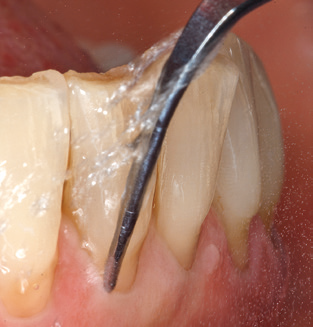

Naturalmente, l'uso di strumenti per la rimozione meccanica del biofilm è una componente centrale di SPT e quindi di importanza primaria. Di conseguenza, il flusso di lavoro SPT comprende sia la pulizia sopra-gengivale che sub-gengivale. Nel nostro piano di lavoro, una combinazione di strumenti manuali e

di dispositivi per la pulizia meccanica si è dimostrata vantaggiosa. Sono disponibili diverse opzioni per le procedure meccaniche: dispositivi sonici, dispositivi ad ultrasuoni e dispositivi di air-polishing.

Una buona illuminazione del campo di lavoro facilita notevolmente il processo. Il sistema utilizzato dagli autori ottiene questo risultato grazie a un anello LED 5x integrato nel manipolo. Naturalmente, viene offerta anche una serie di consigli di lavoro per diverse indicazioni. Un inserto diritto, utilizzabile universalmente, è lo strumento di base necessario per la pulizia meccanica dei denti naturali (Fig. 5a e b). Sono disponibili anche inserti curvi, che consentono l'accesso alle forcazioni esposte, per le aree difficili da raggiungere nella regione posteriore (Fig. 6).

Fig. 4: Sonde flessibili con marcature millimetriche sono consigliate per il sondaggio di impianti dentali (ad es. Colorvue Kit PCV11KIT6, HuFriedy). - Fig. 5a e b: Un inserto diritto (1P, W&H Dentalwerk Bürmoos GmbH) è uno strumento adatto per l'uso su tutti i denti naturali. - Fig. 6: Inserti curvi (3Pr / 3Pl, W&H Dentalwerk Bürmoos GmbH) si prestano alla lavorazione di aree difficili da raggiungere del dente e delle superfici radicolari (ad es. Forcazioni). - Fig. 7: L'inserto esagonale conico per la pulizia dell'impianto (1I, W&H Dentalwerk Bürmoos GmbH) consente una pulizia atraumatica ed efficace della superficie della corona e del moncone. - Fig. 8: Le curette in titanio e carbonio sono strumenti adatti per la pulizia manuale delle superfici dell'impianto.